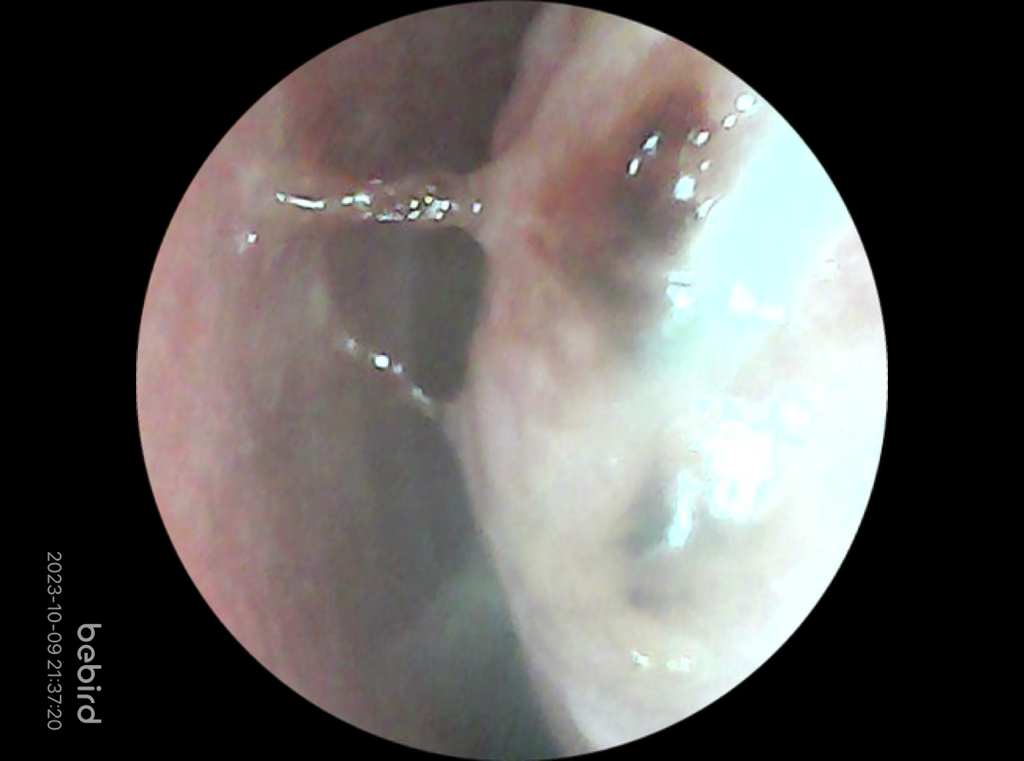

집에 내시경 기능 비슷한 기기가 있어서 찍어봤는데

위쪽이 왼쪽코, 아래쪽이 오른쪽 코 사진이에요

• 1번 째 사진

비강 내 점막의 부종이 관찰되며, 혈관운동성 비염의 경우 치료는 원인 회피 및 증상 호전에 초점을 맞추게 되며, 근본적인 치료는 어렵습니다. 강한 향기, 음주, 매운 음식, 온습도 변화 등 증상을 유발할 수 있는 원인들을 회피하는 것이 최선입니다. 따라서 증상이 심하지 않다면 가정에서 지켜보시고, 증상이 불편한 경우 경구 약물 또는 비강내 스테로이드 스프레이 등을 처방받아 사용해 볼 수 있겠습니다.